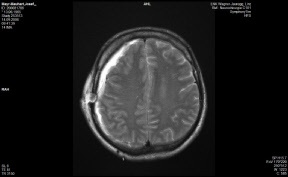

Anbei Daten zur Enthauptung (Heilige Schrift)

Jefferson Fraktur (med. Fachsprache)

Hier habe ich offensichtliche Probleme